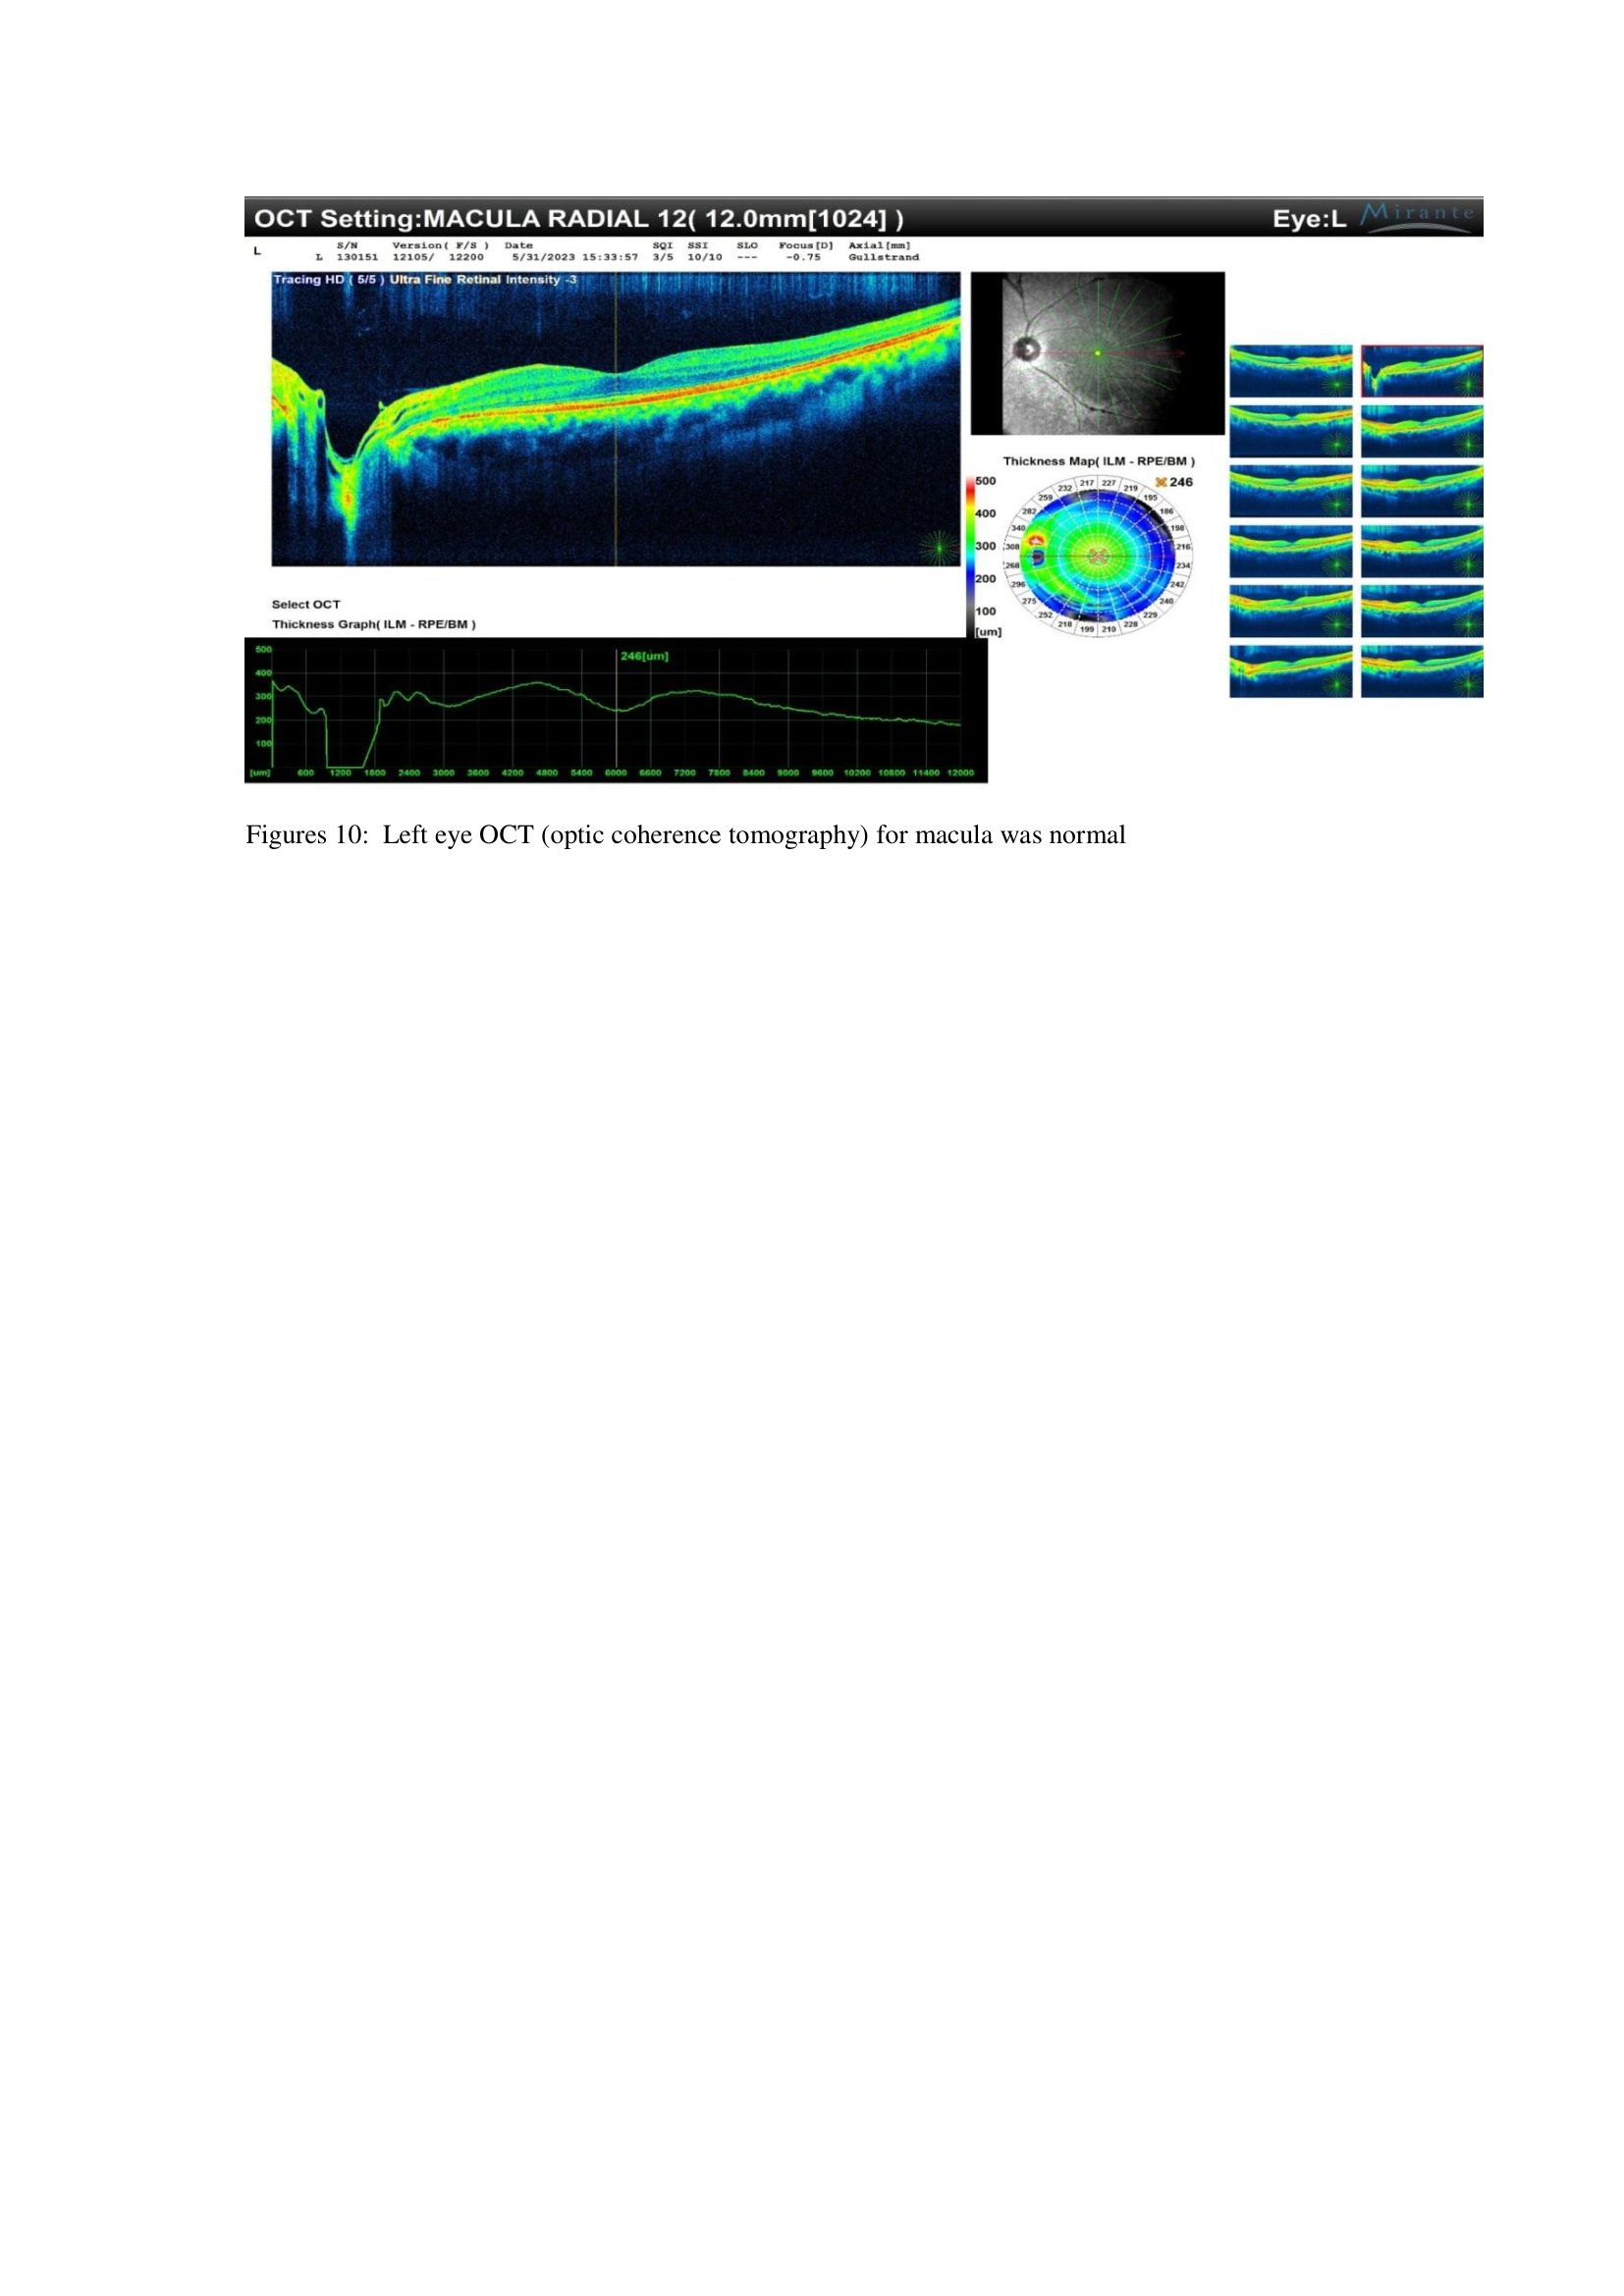

After 12 months, OCT MACULA was done and was normal as shown in figures 9 and 10 below in figures 9 and 10.